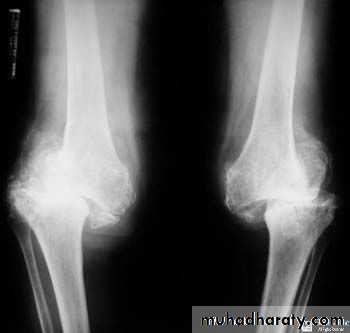

There are three types of arthritis which ca be distinguished radiologically :

1. Degenerative arthritis:Osteophytes

Subcondral sclerosis

Uneven loss of articular space

OA – Radiographic findings1. Joint space narrowing

2. Osteophyte formation (white arrow)3. Subchondral sclerosis (black arrows)

Another example of OA